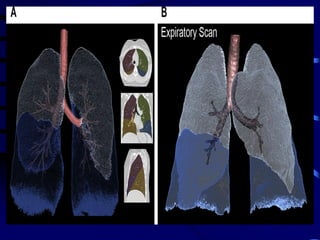

Image-matching methods have been used

(parametric response mapping and disease

probability mapping, whereby inspiratory and

expiratory scans are warped together such

that voxels can be assigned to categories of

air-trapped, normal, and hyperinflated lungs.

MDCT chest image matching. Parametric response mapping and

disease probability mapping methods are demonstrated whereby

inspiratory and expiratory scans are warped together